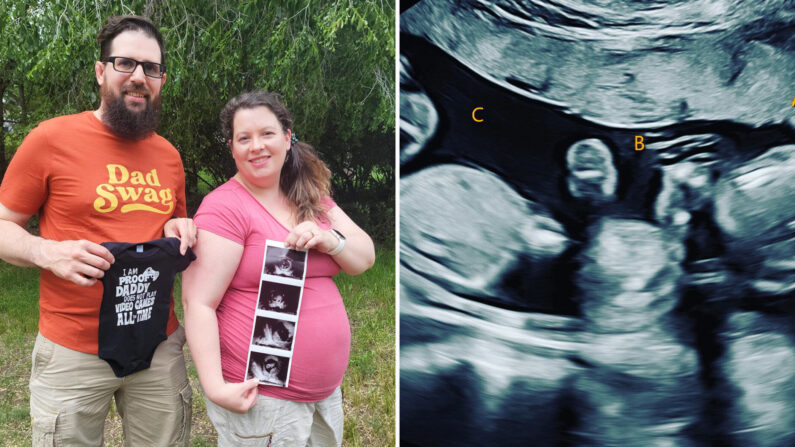

Un couple qui voulait une petite fille était stupéfait lorsqu’il a découvert qu’il attendait non pas une, mais trois filles – des triplées identiques.

« Nous espérions avoir une petite fille, mais maintenant nous en aurons trois », a confié Heather à Epoch Times. « Cette grossesse s’est déroulée de manière totalement naturelle. »

Lors de l’échographie d’Heather, à 8 semaines, le technicien a repéré trois battements de cœur, et peut-être un quatrième.

« J’étais sous le choc », a raconté Heather. « Tyler était si calme et silencieux, mais je n’arrêtais pas de demander aux techniciens : ‘Il n’y en a que deux, n’est-ce pas ?’ ‘Pas plus de trois, n’est-ce pas ?’ »

« Ils ont commencé à étiqueter les bébés de A à C et nous ont laissés voir et entendre les battements de cœur, puis un quatrième sac, le bébé D (…) Je tremblais tellement et je n’arrivais pas à croire ce que je voyais (…) L’idée qu’il y ait des multiples ne m’avait même pas traversé l’esprit. »

Dans les semaines qui ont suivi, la présence du quatrième bébé, un quadruple fraternel, a été confirmée, tout comme le fait que les triplées étaient identiques.

Malheureusement, Heather a perdu le quatrième bébé entre la 11e et la 12e semaine de grossesse à cause d’un phénomène connu sous le nom de « syndrome de lyse d’un jumeau ». Sa grossesse a ensuite été classée comme une grossesse triple monochoriale-triamniotique, ce qui signifie que chacun des trois bébés survivants a un embryon génétiquement identique, mais son propre sac gestationnel.

Heather a fait des recherches en ligne sur la rareté de sa grossesse. « Selon Google, c’est un cas sur 200 millions », dit-elle. Laura Knutson, la gynécologue d’Heather, a dit à la chaîne de télévision KFYR que la probabilité d’avoir des triplés identiques était « probablement d’une sur 100,000, voire plus rare ».